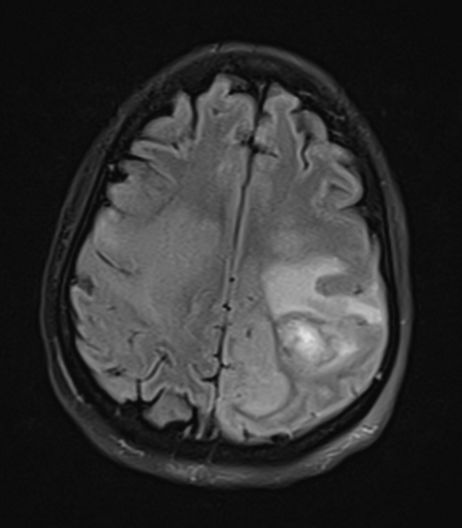

图2 恶性脑梗死的进展过程。在卒中发病的6小时内,CT仅显示额叶、岛叶皮质、颞叶、尾状核和豆状核的轻度密度减低(左);12小时后,可见大脑中动脉和大脑前动脉供血区域边界清晰的梗死区域(中);但没有占位效应。24小时后,病灶出现占位效应,中线移位(右)。